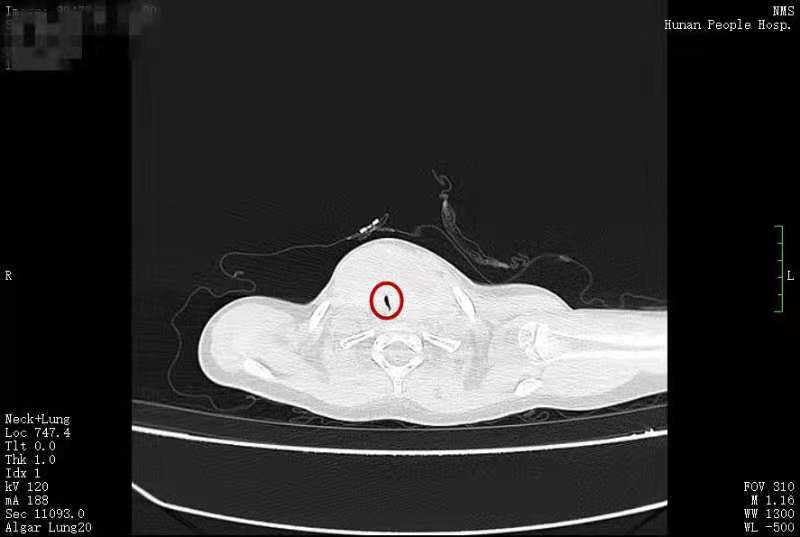

患儿气管被压迫后最细的地方只有3毫米。

没想到这一年来,小丫脖子上的包块快速长大,特别是近3个月,包块从喉部延伸到了耳后,小丫的呼吸也受到了影响。家人再次带小丫来到张超杰教授的门诊,被收治入院。CT结果显示,小丫的甲状腺肿块已经达到了8厘米×5厘米、6厘米×4厘米,而她的气管被压迫成了一条缝,最窄的地方只有3毫米。考虑到小丫的生命将会受到威胁,张超杰教授为她安排了紧急手术。3月30日,在儿童呼吸科、麻醉科的紧密配合下,张超杰教授团队为小丫进行了甲状腺全切手术,术中病理结果显示为甲状腺乳头状癌。手术十分成功,小丫术后返回普通病房,没有出现明显的术后并发症,4月2日出院回家了。